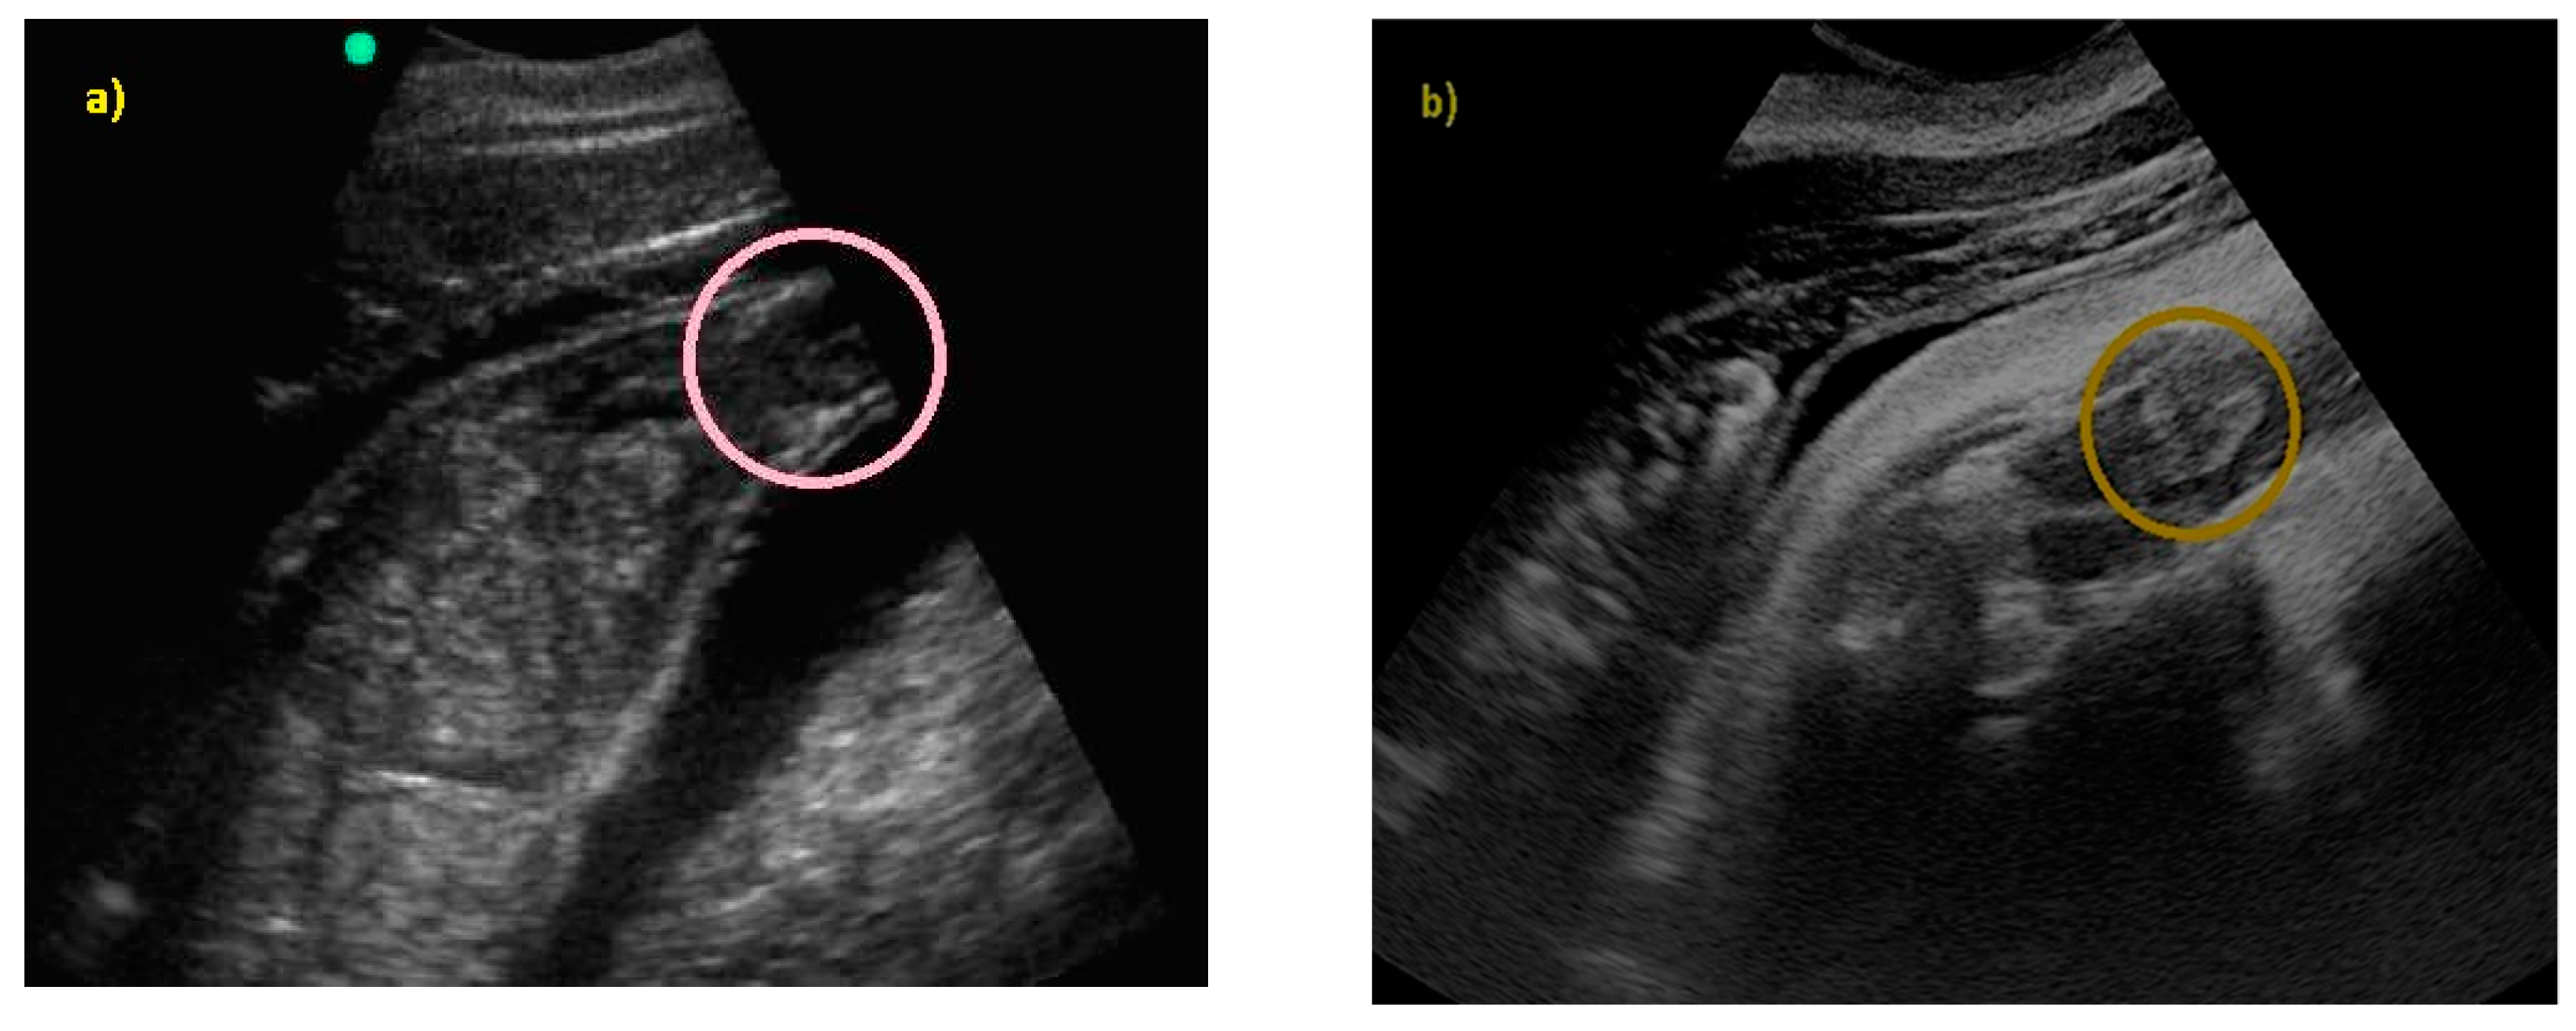

Pregnancy and Fetal Development: Cephalic Presentation and Other Descriptive Ultrasonographic Findings from Clinically Healthy Bottlenose Dolphins (Tursiops truncatus) under Human Care

3. Results